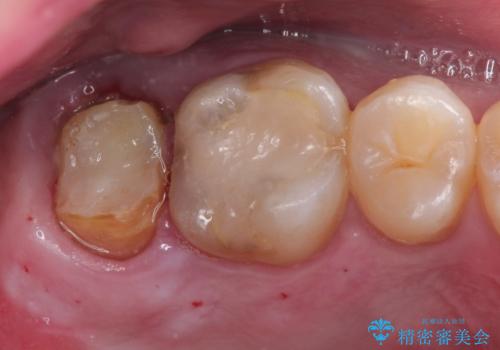

歯肉に埋もれたマージンライン 奥歯の被せもの

- 被せものが取れたことを主訴に来院されました。

以前の被せもののマージンは歯肉縁下に深く形成され、根尖病変も認めたため、根管治療(林先生に依頼)、歯周外科、PGAクラウンにて修復治療を行いました。